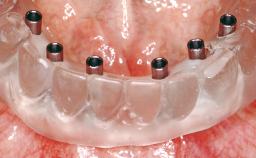

Conventional Loading of Eight Implants in the Maxilla and Final Restoration with a Full-Arch Gold-Ceramic FDP

A 35-year-old Caucasian female presenting with advanced periodontal disease involving both the maxillary and the mandibular dentition was referred for evaluation. The patient, a non-smoker in good general health, requested treatment for recurrent periodontal abscesses, tooth mobility, and discomfort during chewing, as well as restoration of her missing teeth with a fixed prosthesis to improve mastication and esthetics. All residual maxillary teeth exhibited plaque deposits, deep pockets, bleeding on probing, and class III mobility and were evaluated as hopeless. All residual mandibular teeth except tooth 37 could be maintained after periodontal therapy.